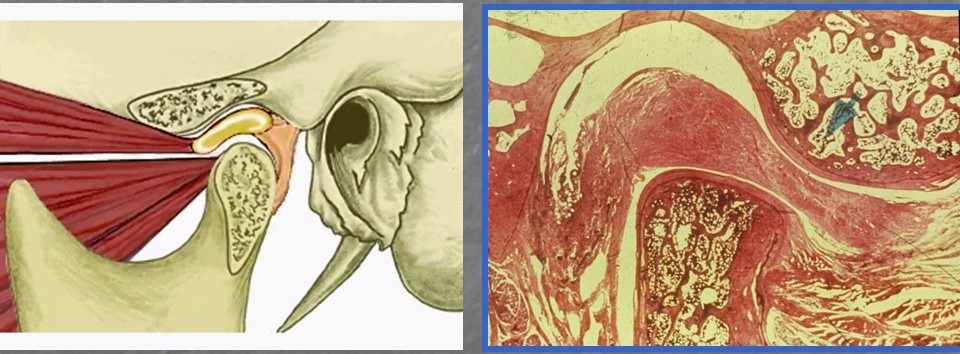

I problemi mandibolari, come il disordine temporomandibolare, possono essere associati a disfunzioni muscolari e articolari che coinvolgono la mascella e le strutture adiacenti. Il dolore mandibolare può irradiarsi verso altre regioni, incluso il collo, causando dolori cervicali. Questa correlazione può essere attribuita a una condivisione di muscoli e nervi tra la regione mandibolare e cervicale.

La muscolatura coinvolta nei movimenti mandibolari e cervicali è intrecciata e interconnessa. I disturbi mandibolari possono influenzare la postura e la funzione muscolare del collo, portando a tensione e dolore cervicale. Inoltre, la disfunzione mandibolare può alterare la stabilità e l’allineamento della colonna cervicale, contribuendo ai dolori cervicali. Questi meccanismi possono essere correlati alla fisiologia del sistema muscolo-scheletrico e alla trasmissione del dolore.

Gli acufeni, comunemente noti come “fischio o ronzio nelle orecchie“, sono suoni percepiti nell’assenza di una fonte sonora esterna. Studi recenti hanno suggerito una possibile connessione tra problemi mandibolari e acufeni. Si ipotizza che la disfunzione mandibolare possa influenzare l’orecchio medio e interno attraverso la tromba di Eustachio, il cui corretto funzionamento è essenziale per la regolazione della pressione dell’aria e la drenaggio dei fluidi. I problemi mandibolari possono alterare il corretto funzionamento della tromba di Eustachio, contribuendo così all’insorgenza degli acufeni.